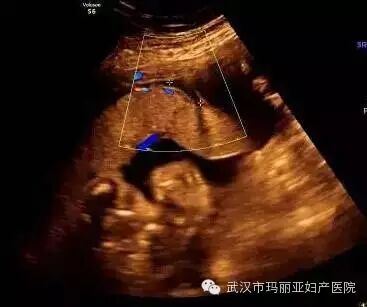

武汉玛丽亚妇产医院引进的世界领先的美国GE-E8四维彩超设备室目前世界上最先进、分辨率最高的彩色超声设备,具有即时立体成像、清晰准确的特点。

它能够多方位、多角度地观察宫内胎儿的生长发育情况,为早期诊断胎儿先天性体表畸形和发育异常提供科学依据。还能对胎儿的体表进行检查,如唇裂、脊柱裂、大脑、肾、 骨骼发育不良等,以便尽早的进行治疗。

玛丽亚美国GE-E8四维彩超排畸成功案例

案例三:肺动脉狭窄